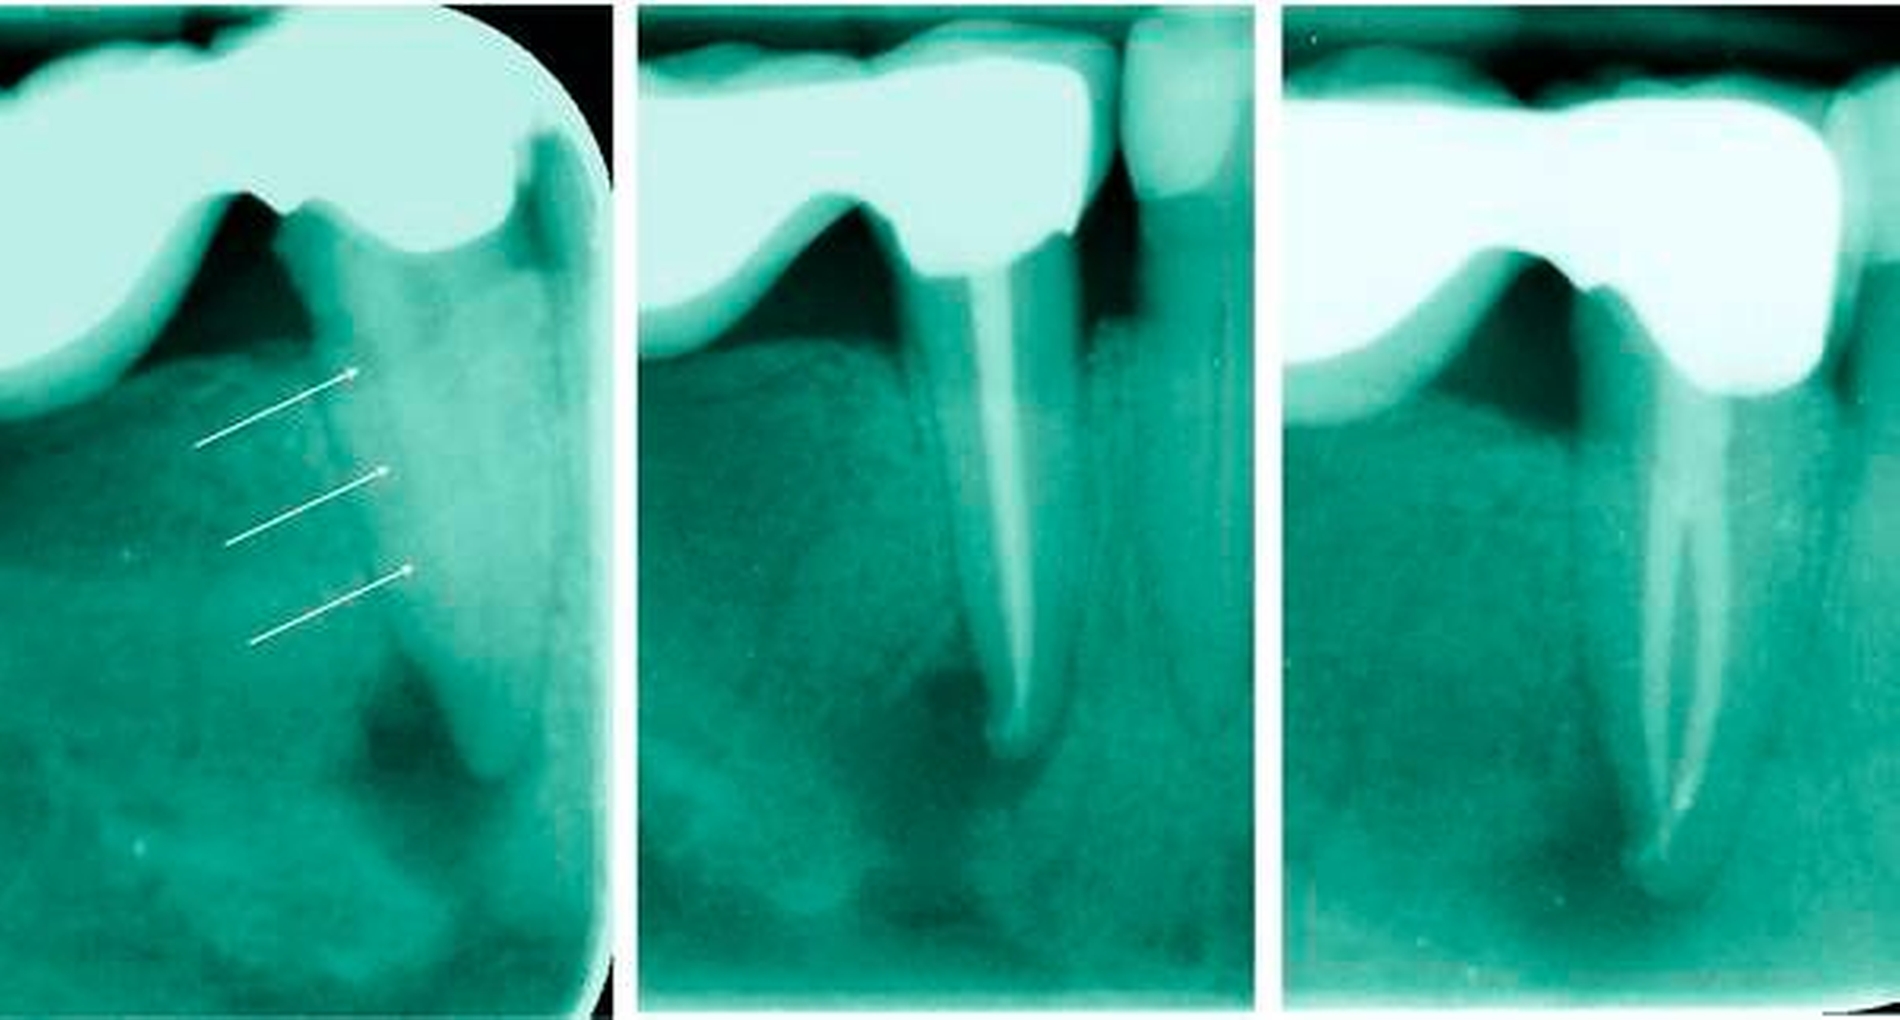

Durch ein genaues Betrachten der präendodontischen, apikalen Röntgenaufnahme können verschiedene Hinweise für das Vorliegen mehrerer Kanäle erkannt werden. Verschwindet ein im Röntgenbild koronal gut sichtbarer Wurzelkanal scheinbar im Verlauf zum Apex oder verengt er sich sehr deutlich, ist das sehr häufig ein Hinweis auf eine Kanalaufzweigung in Strahlenrichtung [England et al., 1991] (Abbildung 9). Weitere Hinweise sind laut Hülsmann [Hülsmann, 2001]:

Neben einer orthograden Aufnahme empfehlen England et al., den Tubus für eine zweite exzentrische Aufnahme im davon abweichenden Winkel von 20 Grad nach mesial oder distal auszurichten [England et al., 1991]. Martinez-Lozano et al. schlagen exzentrische Aufnahmen im Winkel von 20 und 40 Grad vor [Martinez-Lozano et al., 1999], während Rödig und Hülsmann einen Winkel von 30 Grad anraten [Rödig und Hülsmann, 2003].

In einer eigenen Untersuchung unter simulierten klinischen Bedingungen konnte ein zweiter lingualer Kanal am besten bei der Kombination eines orthograden und eines 40° mesial exzentrischen Röntgenbildes entdeckt werden [Rapsch und Paqué, 2017].